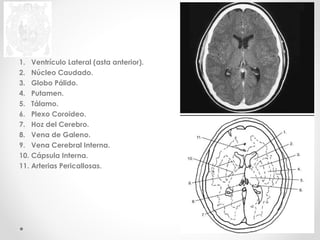

1. Ventrículo Lateral (asta anterior).

2. Núcleo Caudado.

3. Globo Pálido.

4. Putamen.

5. Tálamo.

6. Plexo Coroideo.

7. Hoz del Cerebro.

8. Vena de Galeno.

9. Vena Cerebral Interna.

10. Cápsula Interna.

11. Arterias Pericallosas.